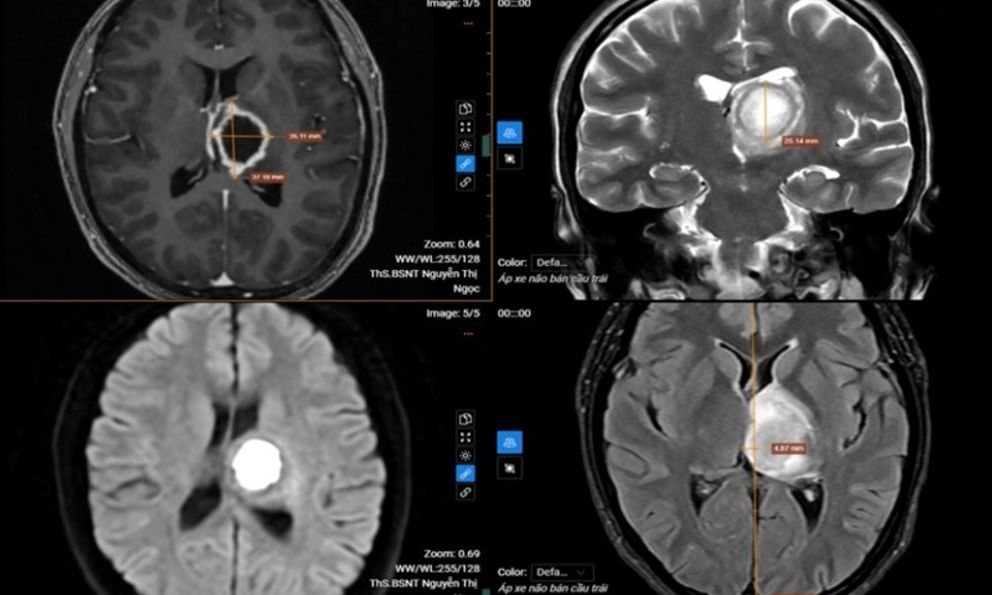

Kết quả chụp cộng hưởng từ (MRI) sọ não phát hiện tổn thương khu trú tại vùng đồi thị – vành tia bên trái, kích thước khoảng 26x37x25 mm. Tổn thương dạng dịch, ranh giới rõ nhưng bờ không đều, trung tâm có hiện tượng hạn chế khuếch tán và ngấm thuốc viền sau tiêm. Vùng não xung quanh xuất hiện phù nề, tạo hiệu ứng khối làm đẩy lệch đường giữa của não sang phải khoảng 5 mm.

Sau khi hội chẩn chuyên môn, các bác sĩ chẩn đoán bệnh nhân mắc áp xe não bán cầu trái và chỉ định nhập viện điều trị nội trú theo phác đồ chuyên khoa để tránh nguy cơ tiến triển nặng. Khi nhận kết quả bệnh nhân đã rất “sốc” vì không nghĩ mắc bệnh lý nghiêm trọng tới vậy.